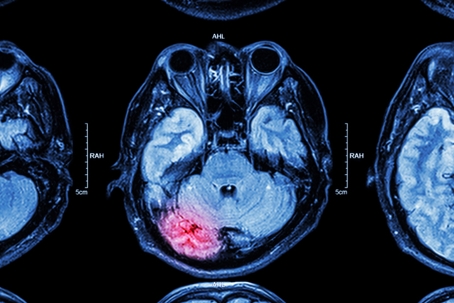

Traumatic Brain Injuries (TBIs) are a significant concern in the aftermath of car accidents. A TBI occurs when an external force causes the brain to dysfunction, often resulting from a violent blow or jolt to the head. In the context of vehicular accidents, TBIs can range from mild concussions to severe brain damage, leading to long-term cognitive and physical impairments.